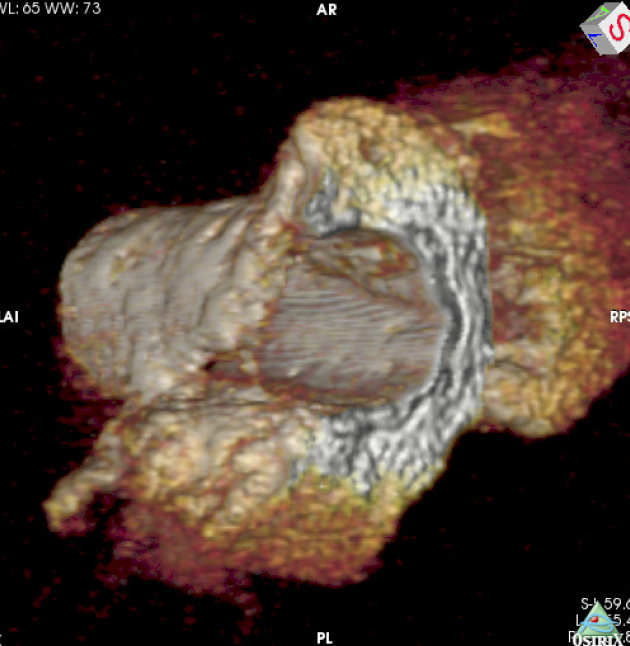

| 3D MR image of porcine duodenum and bile duct, reconstructed from axial slices. |